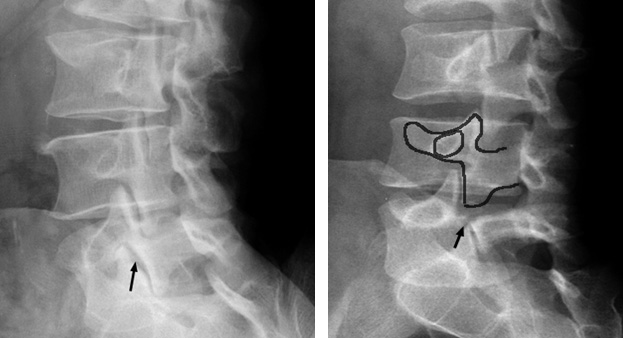

Рентген шейных позвонков при спина бифида

Раздел: Фотозарисовки